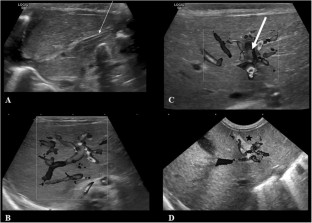

One hundred and twenty-three premature newborns or with birth weight <1.5 kg were prospectively included in a single center during a one-year period. Three systematic abdominal ultrasound examinations at day 3, day 10, and day 45 (and 1 year in case of persistent PVT) were performed. Clinical and biological data were recorded.

Seventy neonates (57%) had three normal US examinations. Fifty-three neonates (43%) had a clinical and biological asymptomatic left PVT. No right or extrahepatic portal venous thrombosis was observed. Umbilical vascular catheter (UVC) was removed in case of PVT. No anticoagulation therapy was required. No risk factor was significantly associated with PVT. At 1 year of follow-up, five infants had persistent isolated left PVT (4%).